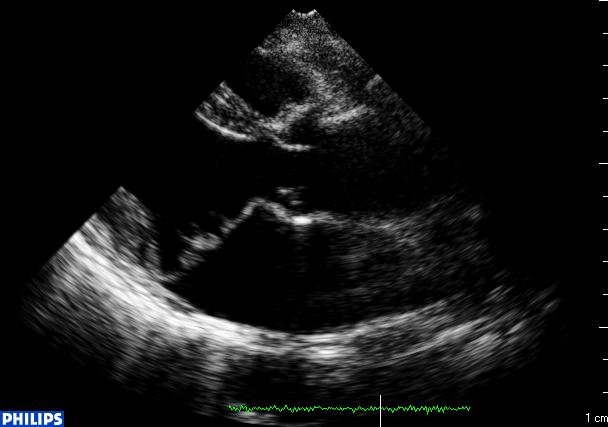

46岁女性RA患者的二尖瓣脱垂的超声图